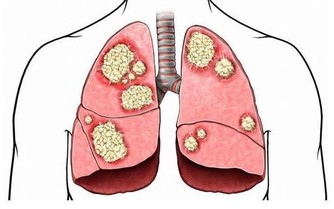

哪些水不能喝? 1、不開的水 膀胱癌、直腸癌。專家指出,飲用未煮沸的水,患膀胱癌、直腸癌的可能性增加21%-38%。當水溫達到100℃,這兩種有害物質會隨蒸氣蒸發而大大減少,如繼續沸騰3分鐘,則飲用安全。 2、千滾水 腹瀉、腹脹、昏迷驚厥。千滾水就是在爐上沸騰了一夜或很長時間的水,還有電熱水器中反覆煮沸的水。這種水因煮過久,水中不揮發性物質,如鈣、鎂等重金屬成分和亞硝酸鹽含量很高。久飲這種水,會干擾人的胃腸功能,出現暫時腹瀉、腹脹;有毒的亞硝酸鹽還會造成機體缺氧,嚴重者會昏迷驚厥,甚至死亡。 3、蒸鍋水 早衰、癌症。蒸鍋水就是蒸饅頭等剩鍋水,多次反複使用的蒸鍋水亞硝酸鹽濃度很高。常飲這種水,或用這種水熬稀飯,會引起亞硝酸鹽中毒,水垢經常隨水進入人體,還會引起消化、神經、泌尿和造血系統病變,甚至引起早衰、癌症。 4、老化水 食道癌、胃癌。俗稱「死水」,也就是長時間貯存不動的水。常飲用這種水,對未成年人會使細胞新陳代謝明顯減慢,影響身體發育;中老年人則會加速衰,許多老地方食道癌、胃癌發病率日益增高,可能與長期飲用老化水有關。老化水中的有毒物質也隨著水貯存時間增加而增加。 |